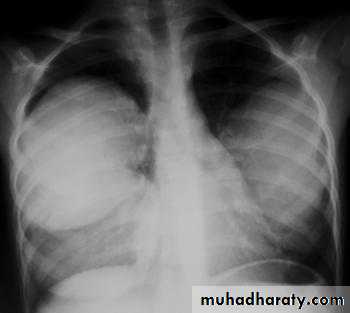

X-ray of pleural effusion

Massive right effusion